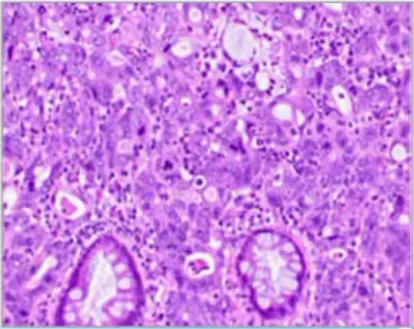

混合性肝细胞癌-胆管细胞癌(cHCC-CCA)

• 必要标准:一种双表型PLC,基于H&E形态显示出明确的肝细胞和胆管细胞分化特征;仅免疫组织化学标志物的表达,而无组织形态学特征,不足以作出诊断

• 理想情况:在大多数情况下,最佳做法是通过免疫组织化学染色来确认形态学分化。

• 备注:

1.cHCC-CCA的HCC成分和CCA成分可相互靠近或深度混杂;

2.cHCC-CCA的诊断不受每种成分所占百分比的影响;

3.cHCC-CCA患者的治疗会根据肿瘤的主要成分来确定,且这一信息应纳入病理报告中

4.小而均一的肿瘤细胞具有干细胞特征(胞质稀少,核仁不明显)在两种成分之间的过渡区、肝细胞癌小梁的边缘出现;

5.罕见的cHCC-CCA可包含单独NEC成分。